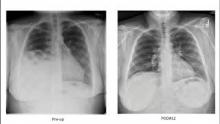

This is a case presentation including intraoperative video of a robotic-assisted laparoscopic repair of a hernia of Morgagni.